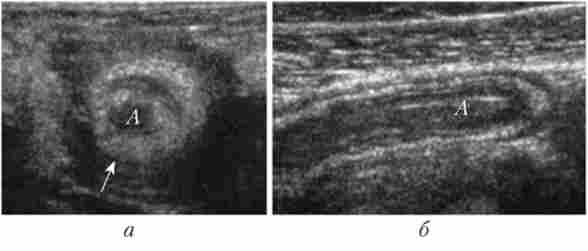

Візуалізація нормального апендикса можлива не завжди (приблизно в 30% випадків). При деструктивних формах апендициту цей показник зростає приблизно до 80%. Запалений відросток видно як трубчаста структура з шаруватою стінкою, що відходить від сліпої кишки. Він не пери стальтірует і не стискається при дозованої компресії черевної стінки датчиком. Характерно виразне потовщення стінки і збільшення діаметру органу в порівнянні з нормою (рис. 22.3).

Мал. 223. Ультразвукова картина при гострому флегмонозном апендициті. поздовжній (А) і поперечний (Б) зрізи апендикса (Л), отримані при ультразвуковому скануванні правої клубової області. Апендикс представляється трубчастої структурою з расслоенной і потовщеною (вказано стрілкою) стінкою

В просвіті можуть визначатися як в'язке вміст (рідкий кал, гній), так і копроліти.